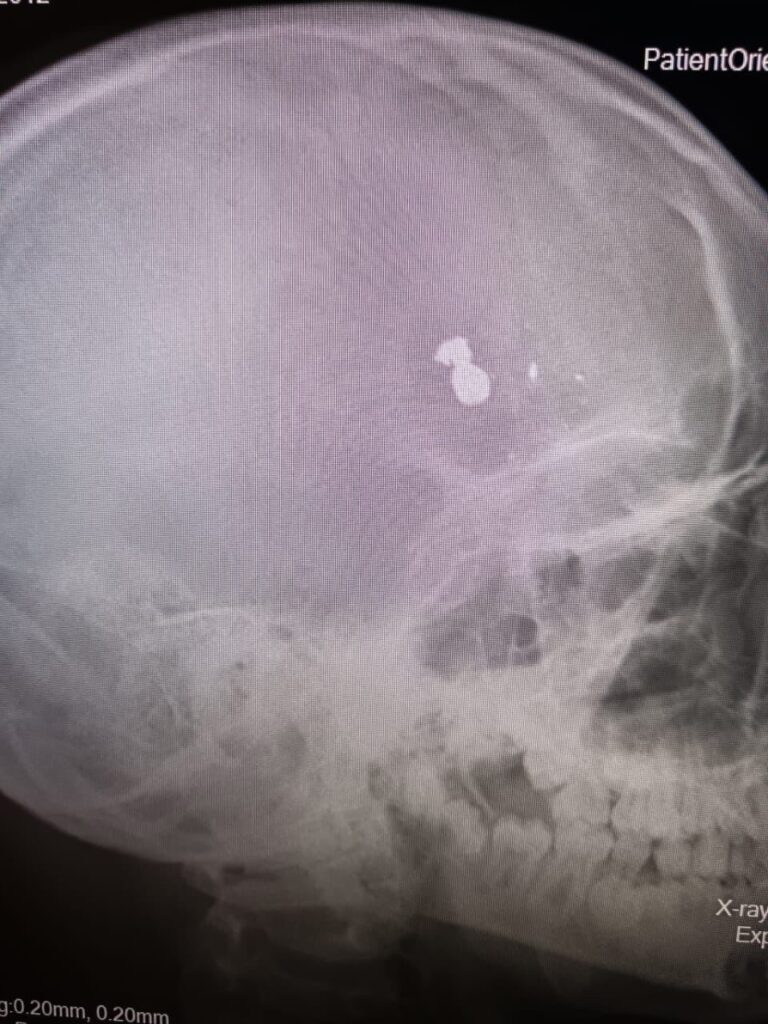

В Дергачевскую районную больницу был доставлен 12-летний мальчик, который при невыясненных обстоятельствах получил огнестрельное ранение головы. Он был немедленно переведен в детскую областную больницу, где операционная бригада приступила к операции, которая длилась около пяти часов.

Министерство здравоохранения Саратовской области сообщило о ходе операции и опубликовало фотографии. В результате операции инородные тела, включая пулю и осколки, были успешно удалены. Тяжесть состояния пациента соответствует объему проведенной операции, и оперативное лечение было выполнено в полном объеме. В настоящее время продолжается наблюдение за состоянием ребенка.